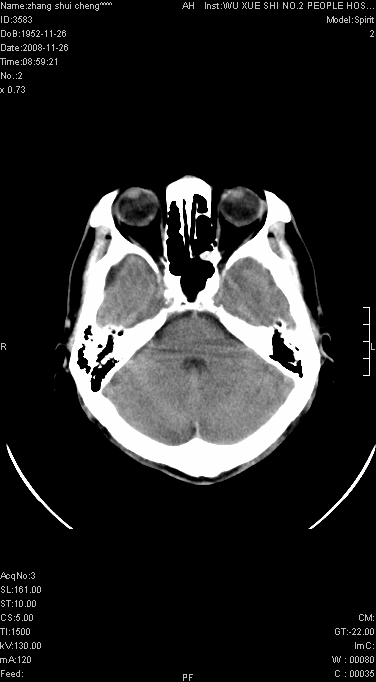

男.68.肢体无力多年

请问是蛛网膜囊肿.还是软化灶.原有中风

脑外性,蛛网膜囊肿

支持右侧颞区蛛网膜囊肿。

蛛网膜囊肿,软化灶周围脑沟应该受牵拉,扩大